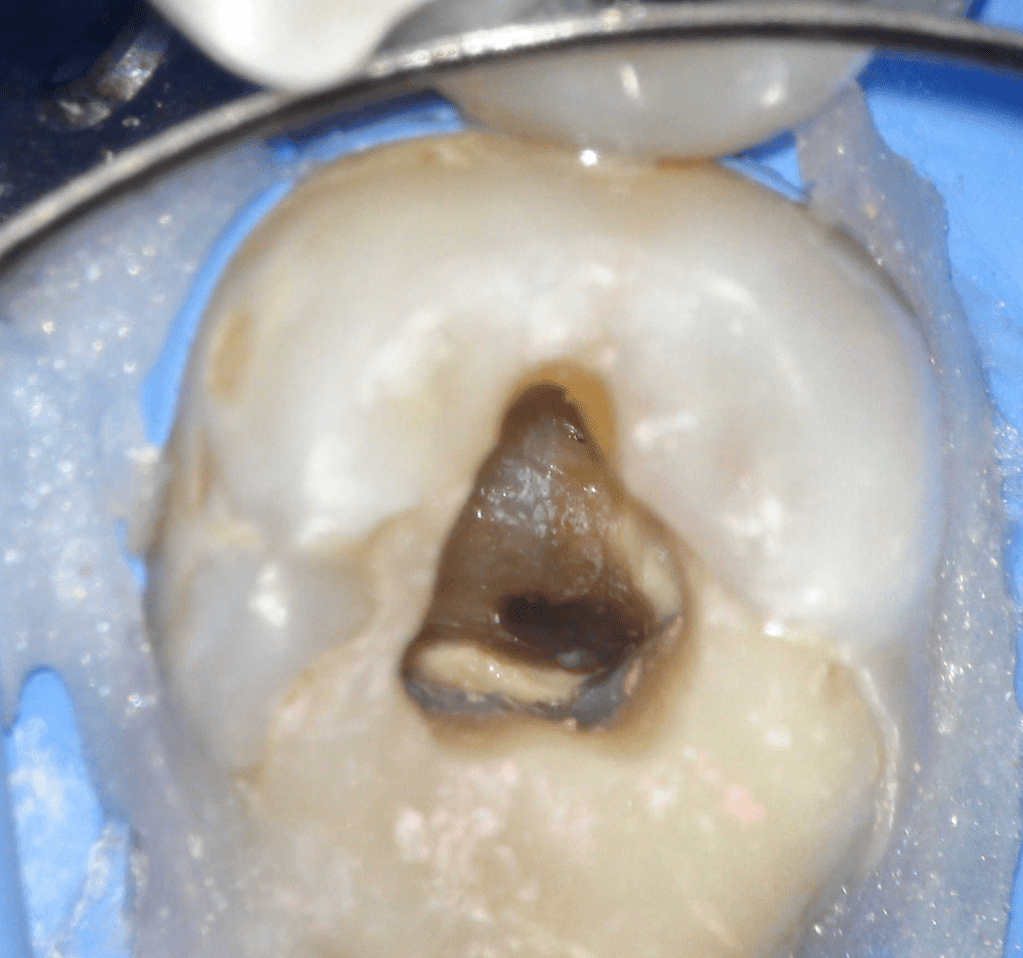

Pulpotomía biodentine + reco preendio